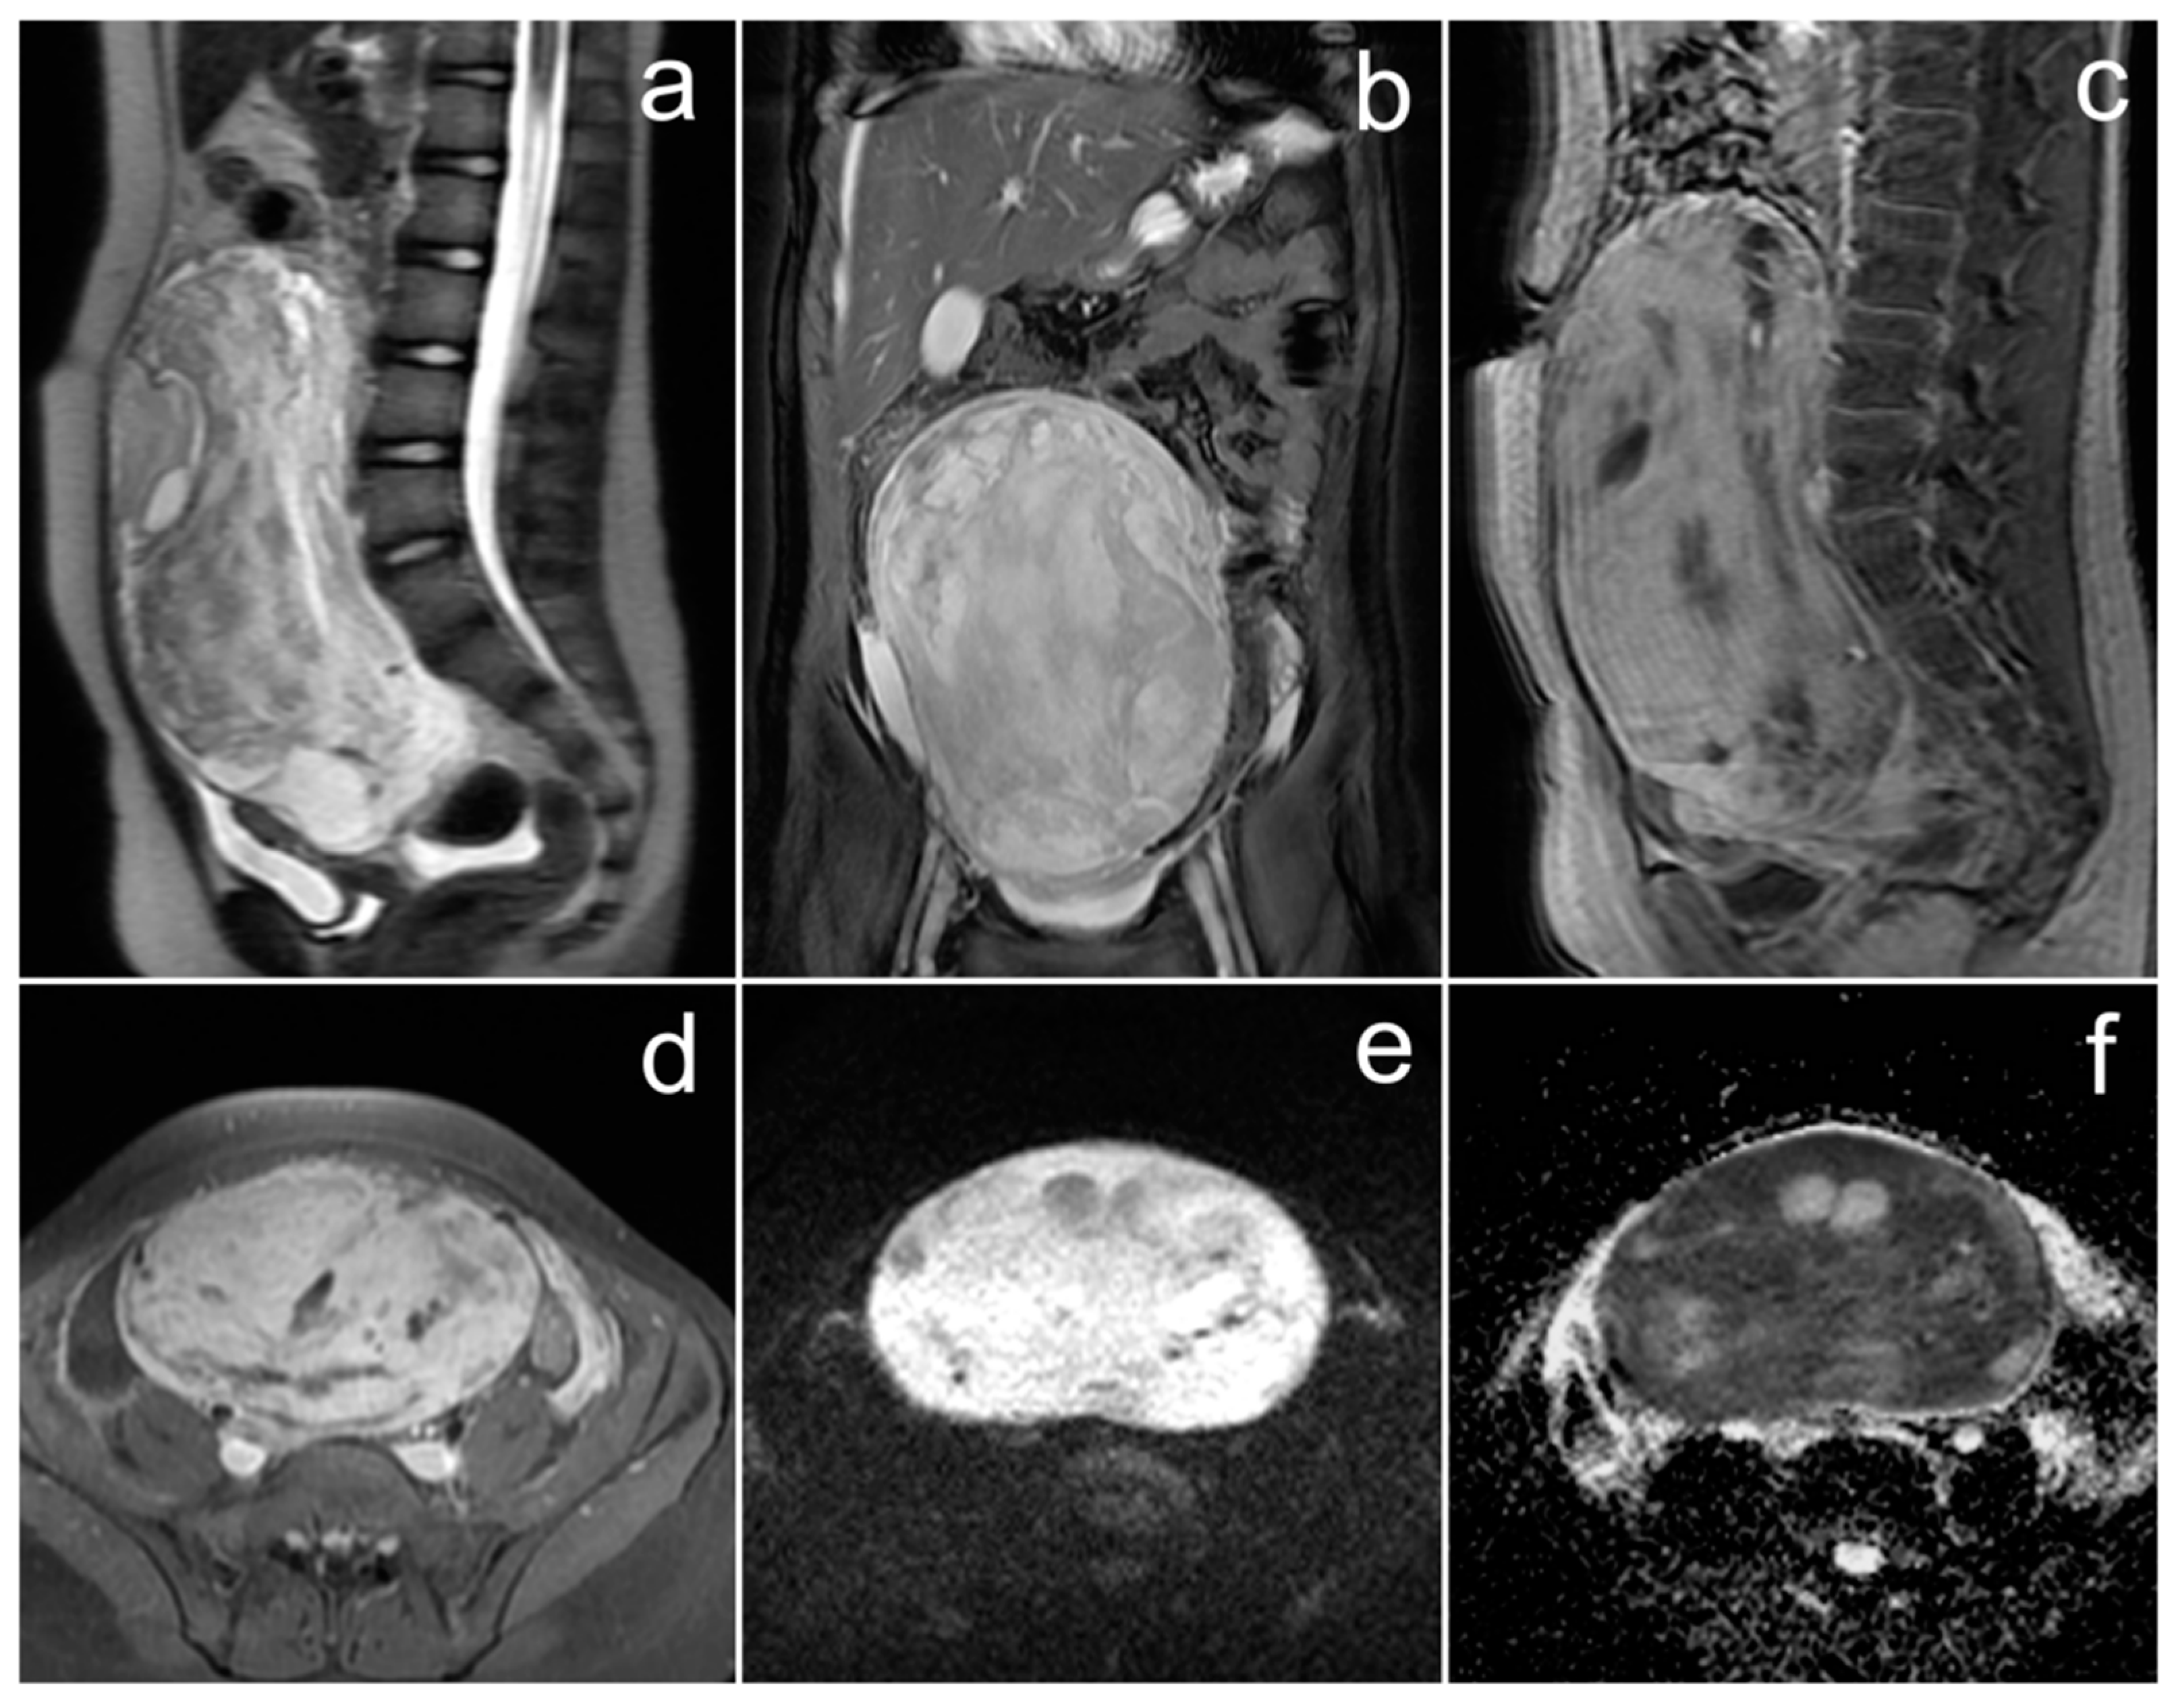

3.1. Small Cell Carcinoma of the Ovary, Hypercalcemic Type

Case Report

| Small cell carcinoma of the ovary, hypercalcemic type | non-specific; unilateral, sizable mass with central necrosis or calcifications | hypercalcemia | symptoms associated with hypercalcemia: polydipsia, constipation, polyuria, bone pain, muscle weakness |